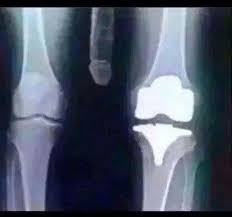

Find x ray of knee stock images in hd and millions of other royalty free stock photos illustrations and vectors in the shutterstock collection. Add to likebox 127713977 wheelchair icon simple style. X ray image of right knee ap and lateral view showing total knee arthroplasty and fractures of the tibial plateau with. This x ray shows a healthy joint with nice sharp well defined edges at the joint margins.